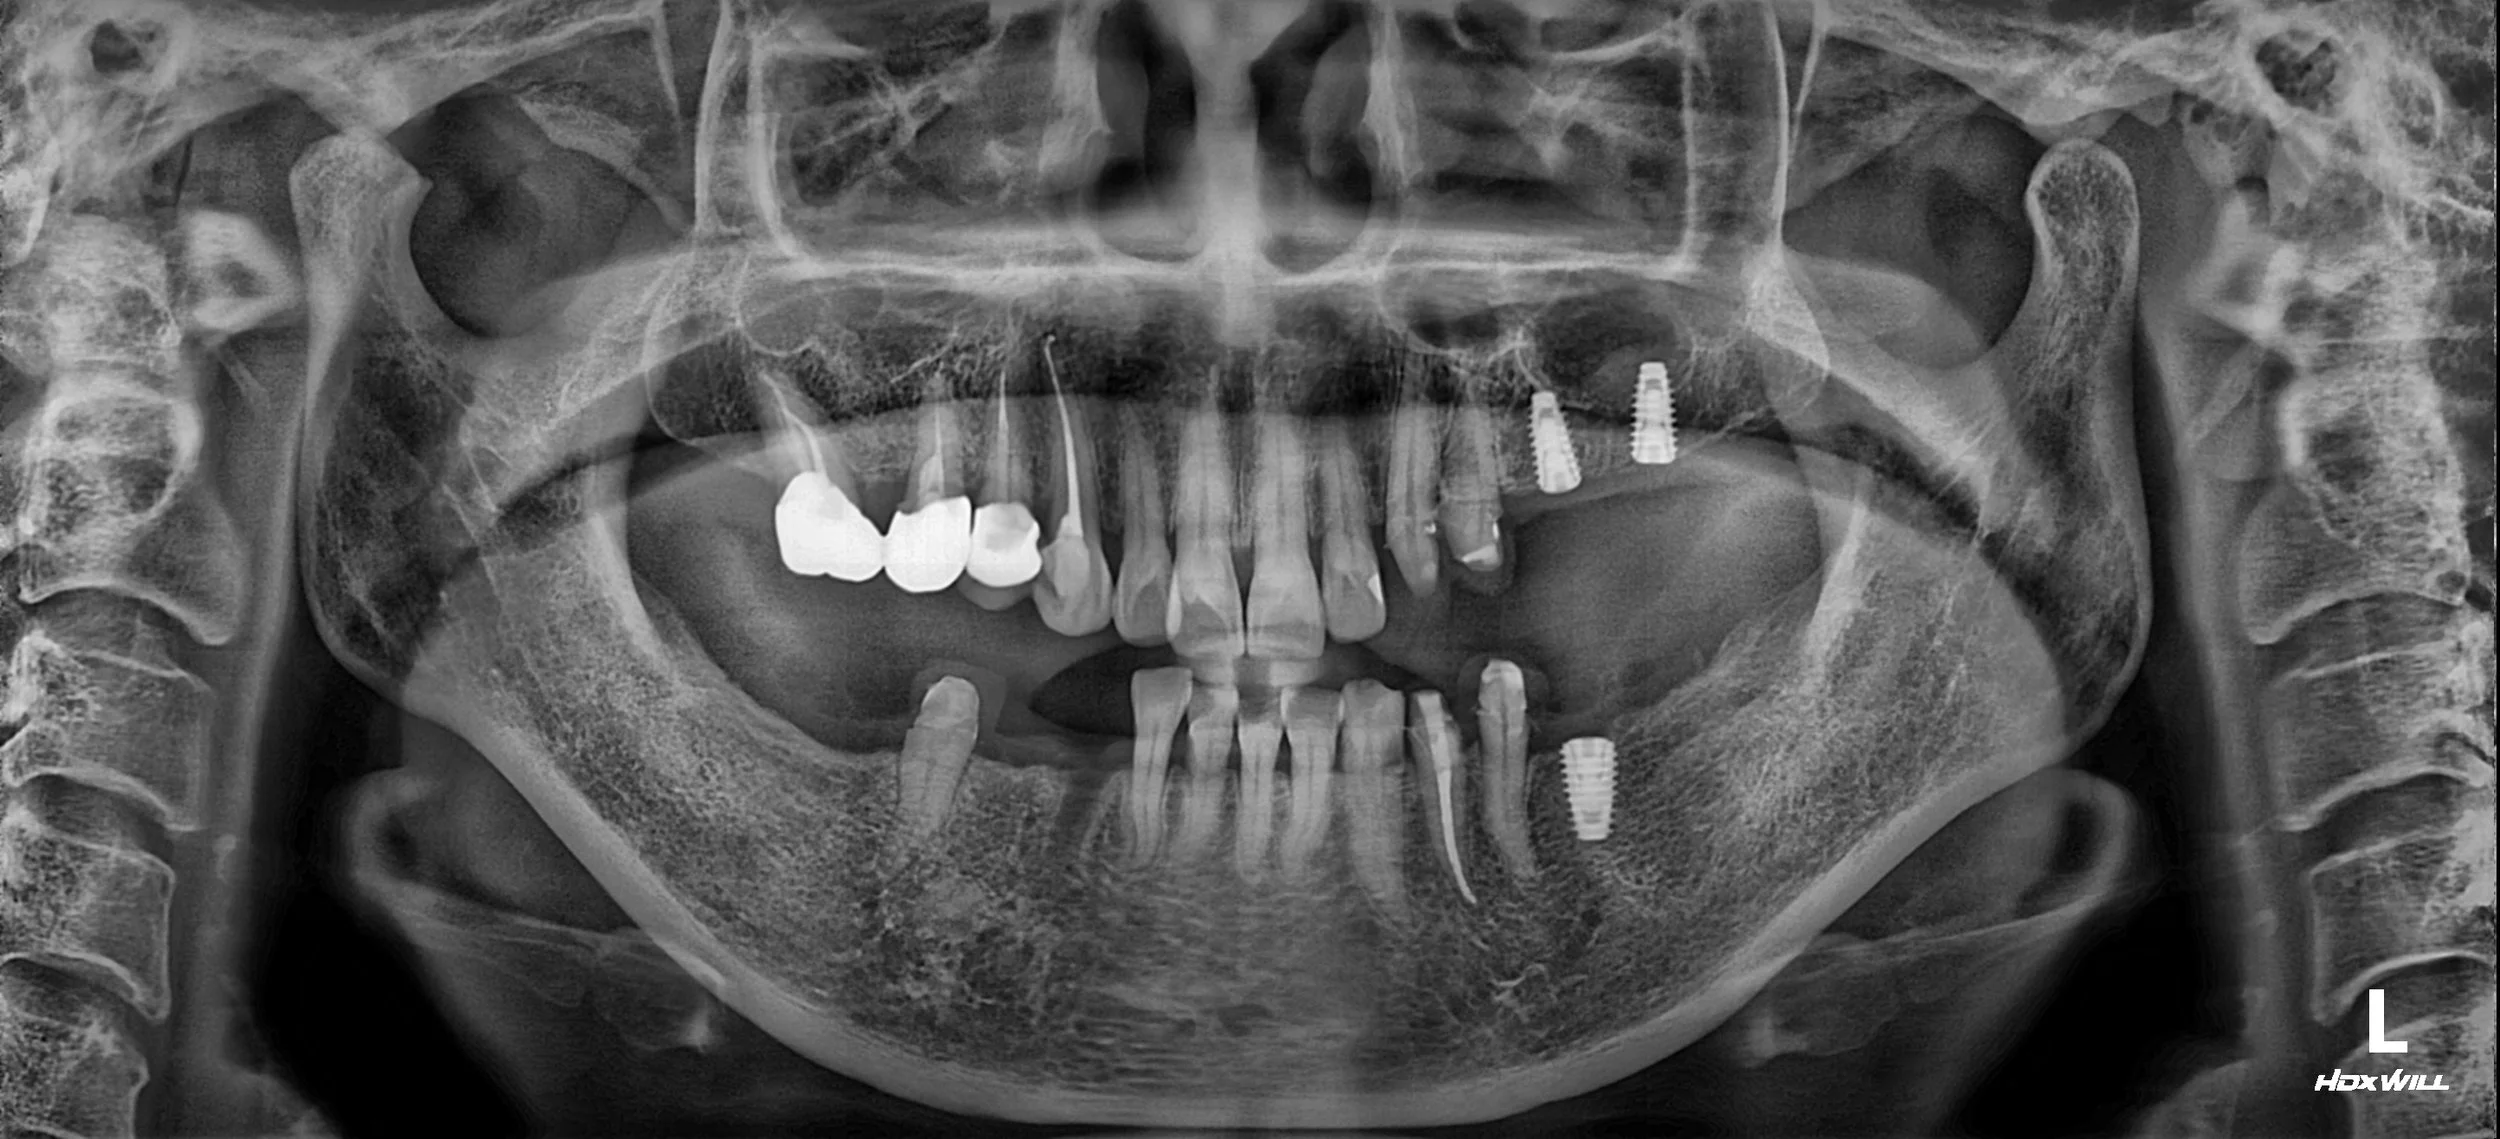

OPG - BEFORE